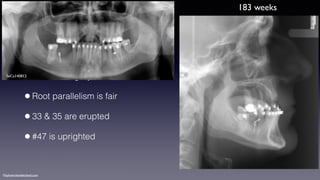

•Prior to surgery

•Root parallelism is fair

•33 & 35 are erupted

•#47 is uprighted

183 weeks